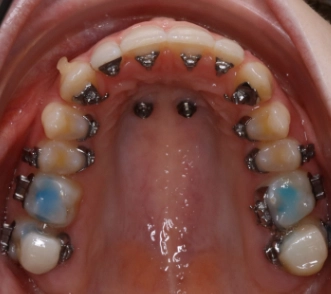

digitale Pin Planung

2 Gaumenpins

Nach einer ganzheitlichen Erstuntersuchung Teenager folgt eine ausführliche Erstbesprechung der Untersuchungsergebnisse mit den Eltern und der Patientin.

Bei jedem Termin kontrolliert eine Zahnärztin den Behandlungsfortschritt während Kieferorthopädie in Wolfratshausen.